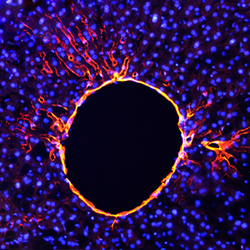

AF8299 IHC

Full details

Method:

Other validation